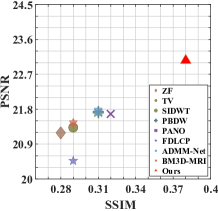

First, we test on 25 T1-weighted MRI data using three different undersampling patterns with a fixed 10% sampling rate. Fig. 3 shows the quantitative results (PSNR). Our method performances best for all three cases and has stronger stability compared with the second best method on variance. As for the effect of sampling ratios variation, we use radial mask under 10%, 30% and 50% sampling rates with evaluation of RLNE and MSE. Fig. 4 shows that our method has the lowest reconstruction error for all sampling rates. For more intuitive comparison, we illustrate the reconstruction error in term of pixels in Fig. 5. We also offer the qualitative comparison in Fig. 6. Visualized results demonstrate our method has better performance in both artifacts removing and details restoration. Time consuming is also considered. We compare our method with others on the 25 T1-weighted data using Radial mask with 10% and 50% sampling rate. Notice that ADMM-Net and ours are tested on GPU for the incorporation of deep architecture. Tab. 1 shows that our method provides an efficient reconstruction process and comes to the fastest method among the state-of-the-art competitors.